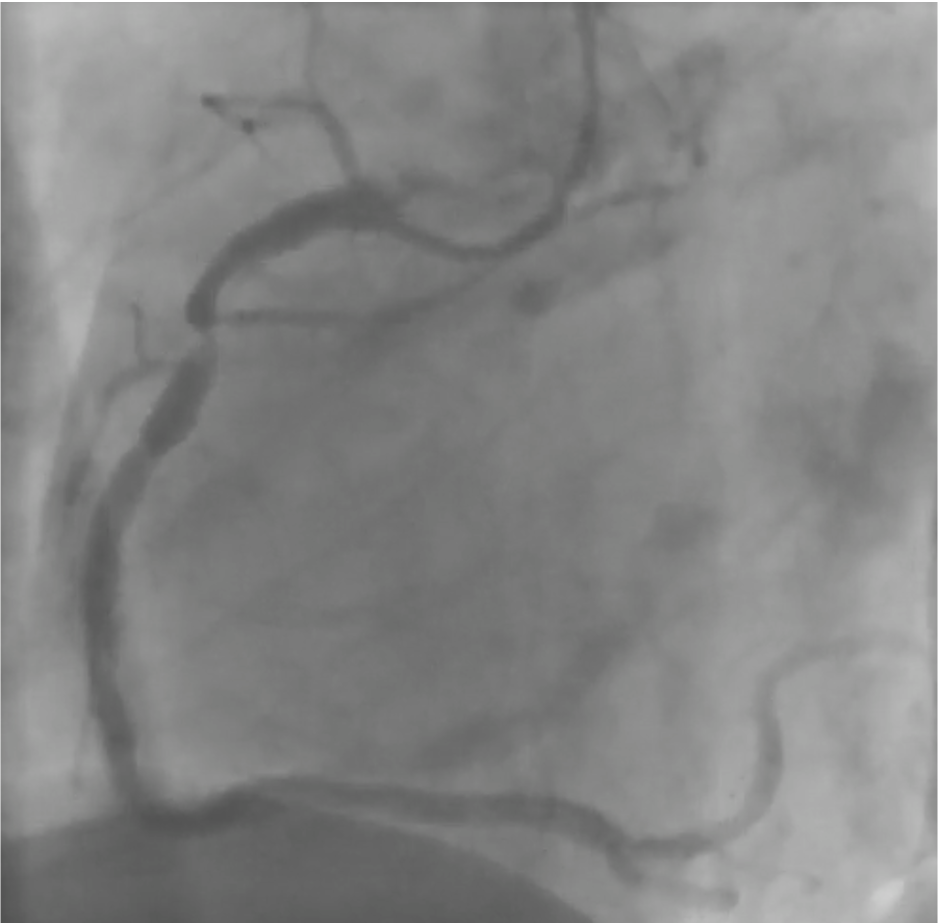

Coronary angiography via left distal radial access revealed two-vessel coronary artery disease. A true LAD–Diagonal bifurcation lesion (Medina 1.1.1) was noted, with 80% stenosis in the LAD middle segment and 80% stenosis at the D2 ostium. The proximal RCA showed critical 99% stenosis. Resting coronary physiologic indices showed: LAD-O 0.99, LAD-M 0.73, LAD-D2 0.80